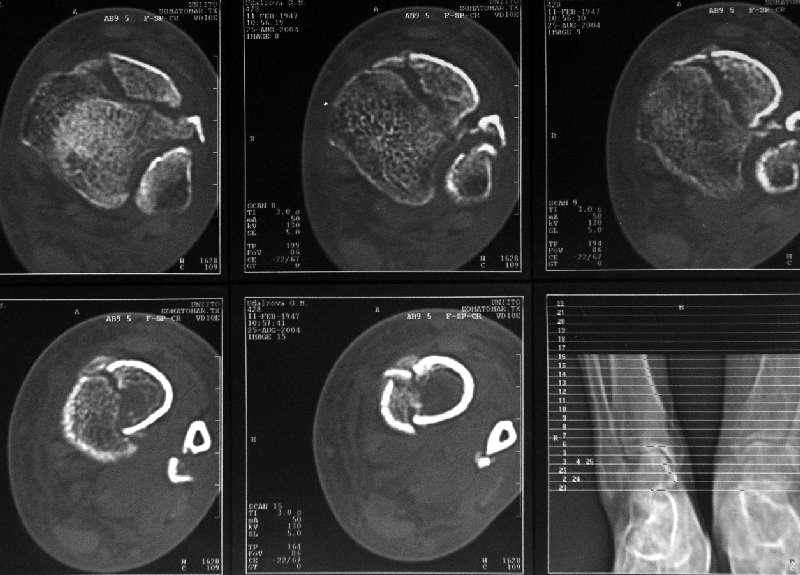

Дама 56 лет 6 недель назад получила спиральные переломы дистальных отделов костей голени. По месту жительства наложили гипс.

Сейчас вот, получается, спохватились. Снимки и КТ в приложении. Какой вариант тут предпочтительнее - открытая мобилизация, репозиция и внутренняя или наружная фиксация? Или ограничиться только резекцией костного шипа над шейкой тарана?Заранее спасибо.A female 56 y.o. 6 weeks ago sustained a fracture of the distal tibia/fibula. At the initial hospital a plaster cast was applied. Now she was referred to our unit. At the moment there is no pain, no obvious mobility. Images and CT attached.What is the best option here? Mobilize the fracture, perform open reduction and internal or external fixation? Or just to cut the anterior spike over the talar neck? THX in advance.

The anterior spike seems to be more antero-lateral, rather than anterior, in such a position that it may not hamper dorsiflexion.

The ankle mortise as a unit is intact.

Здесь повреждение не диафизарное, смотрели состояние суставного конца кости и взаимоотношения таранной кости с этим шипом. Результаты КТ как раз повлияли на план, без нее пошли бы латеральным доступом, а после - передне-медиальным.

Уменьшение риска до минимума, то есть удаление выступающей части кости, который можно более информативно увидеть на компьютерной томограмме, по моему мнению, было разумным решением. (зачем экономить, если имеются показания)